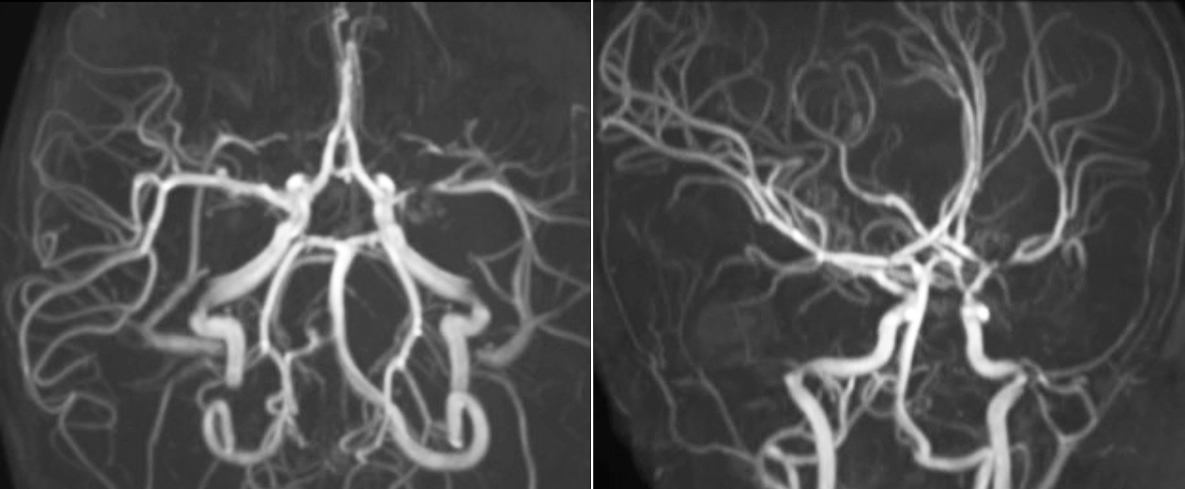

Pseudo-continuous arterial spin labeling (pCASL) was developed for brain perfusion imaging without contrast agent. “This is very desirable in pediatric patients where the general trend is to limit the administration of contrast,” says Dr. Miller. Growing confidence in specific applications “We built up confidence in pCASL by comparing it to contrast-based perfusion imaging. Once we had confidence that it was representing what the contrast perfusions were representing, we increased our diagnostic confidence by serial imaging in either the acute stage or the long term stages in a number of patients with arterial abnormalities.

Dr. Miller uses pCASL for all patients who present with chronic and acute cerebrovascular abnormalities such as acute stroke, as well as patients who present with signs of acute inflammation in the brain, and occasionally in patients with tumors, to assess the perfusion status of their tumor.

“In combination with diffusion weighted imaging, it can help give a more extended assessment of the degree of perfusion abnormality in a patient who is suffering acute ischemia. We have a number of patients who have chronic arterial insufficiency due to prior arterial abnormalities or acquired arterial abnormalities such as sickle cell disease or neurofibromatosis. Sometimes the child’s first manifestation of disease progression is a reduction in brain perfusion before stroke symptoms manifest clinically or in diffusion weighted imaging. We use pCASL to help delineate the perfusion abnormality.”

To other new users I would recommend to also start to interpret the pCASL images in comparison with other standard imaging – T2 and FLAIR and DWI – until the user gains confidence in interpreting these images by themselves.” “A powerful use of pCASL is in patients with chronic cerebrovascular stenosis, where clinicians desire information on how compensatory mechanisms of the brain are performing to enable perfusion to the brain. Often clinicians take into account how the compensatory mechanisms appear to help to provide adequate perfusion to the patient’s brain, and they may intervene surgically or make some other management decision.” “Another special application is the assessment of cerebrovascular reactivity with a Diamox perfusion exam, where we subtract two sets of pCASL images.”